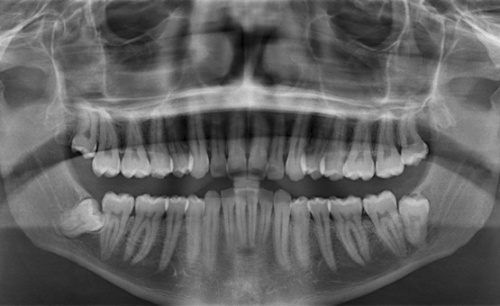

Ортопантограмма (панорамный снимок) — это одна из разновидностей классической цифровой рентенографии, которая позволяет получить качественное изображение внутренних анатомических структур верхней и нижней челюсти, пазух черепа. Панорамный снимок незаменим при составлении плана протезирования, имплантации зубов и ортодонтического лечения. Недорого сделать панорамный снимок в Минске можно на уникальном оборудовании, которое отличается предельным качеством изображения и незначительной лучевой нагрузкой - рентген-аппарат Sirona, производства Германии. Данное устройство обладает возможностью послойного сканирования, что делает его использование незаменимым при имплантации зубов.